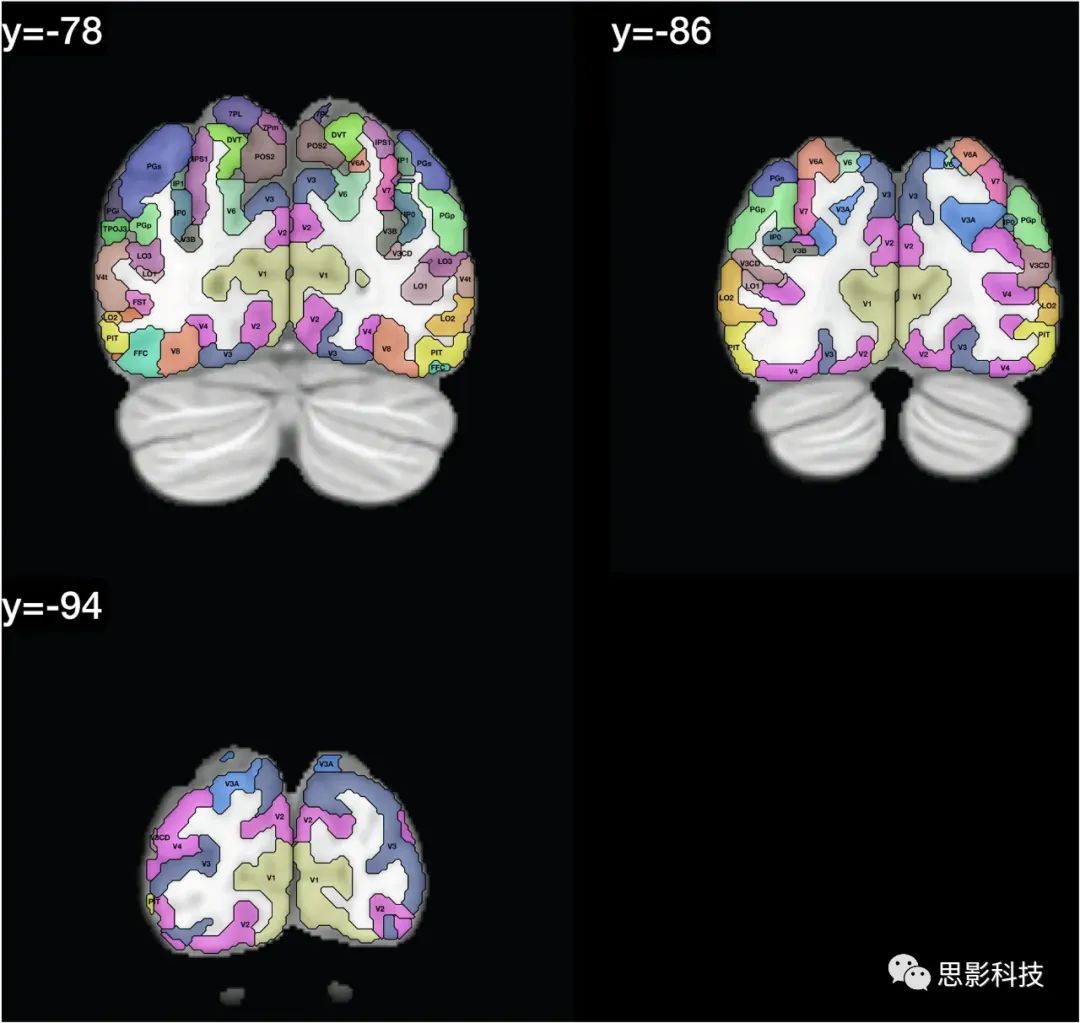

在人类连接组计划(HCP)图谱中区域的定义显示在Glasser et al.(2016a, b)的Glasser_2016_Table.xlsx中。这些区域的列表提供在表1中,并且在图1中,我们展示了带有在HCPex图谱中定义的区域标签的冠状切片。图1中的皮层区域是按照人类连接组计划(HCP)图谱(Glasser et al. 2016a)中的定义来的。

图1:展示了HCPex图谱中定义的区域和新增的皮层下区域的示例冠状切片。这些切片中使用的缩写与表1中的相同。这些冠状切片的y轴坐标是根据MNI(蒙特利尔神经学研究所)坐标系统来确定的。

图1提供了扩展HCP图谱的标记版本,以帮助读者识别这些人脑冠状切片中的脑区域。值得注意的是,一些小的脑结构在这些冠状切片中可能显得非常小,因为它们是被8毫米分隔开的(例如隔核就位于MNI坐标y:3–10之间)。表1和表2提供了图谱中脑区域的列表。在这个重新排序的列表中,标签列表提供在HCPex_LabelID.mat中。

本文描述的HCPex图谱扩展了HCP-MMP1图谱(Glasser et al. 2016a),通过增加66个皮下区域,以体积(volume)形式提供以适用于多种类型的神经影像软件,包括SPM,提供带标签的大脑冠状切片以清晰可视化HCPex图谱中定义的皮层和皮下区域(图1),并提供图谱中皮层区域的可选重排序(表1)。我们已经发现,有了这些扩展,HCPex图谱非常有帮助(Huang et al. 2021; Ma et al. 2021; Rolls et al. 2021)。

总之,这里描述的HCPex图谱通过增加66个皮层下区域、以体积(Volume)形式提供以适用于多种类型的神经影像软件(包括SPM)、提供带标签的大脑冠状切片以清晰可视化HCPex图谱中定义的皮层和皮层下区域(图1)以及提供图谱中皮层区域的可选重排序(表1),从而扩展了HCP-MMP1图谱(Glasser et al. 2016a)。